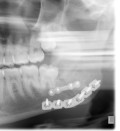

Facial Fracture X-Rays